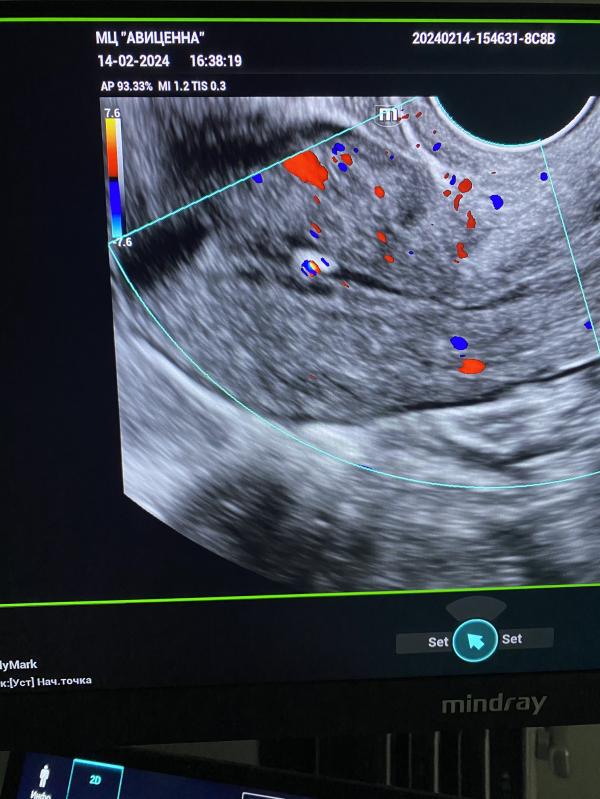

post image 3